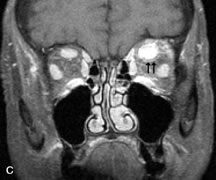

Pleomorphic adenomas demonstrate long T1 and T2 signal characteristics. They may show heterogeneity on T2-weighted images74 and moderate to marked enhancement with contrast.75 Signal characteristics of adenoid cystic carcinoma include hypointensity to fat on T1-weighted images, hyperintensity to fat with increased T2 weighting, and isointensity to fat on proton density-weighted studies (Fig. 23).31,75 Secondary bony alterations of the lacrimal fossa associated with lacrimal gland tumors, such as remodeling (benign mixed tumor) or destruction (adenoid cystic carcinoma), are seen indirectly on MR images; however, bone windows on CT scans provide better delineation of these changes. In contrast to the round or globular appearance of benign or malignant epithelial tumors of the lacrimal gland, lymphoproliferative tumors usually appear to be molding or draping onto the globe and the surrounding bony orbit.

Fig. 23. A. T2-weighted and (B and C) postcontrast fat-suppressed T1-weighted MR scans demonstrate an infiltrative lacrimal region mass than invades the lateral rectus muscle (arrows). This highly cellular lesion is seen to have a very hypointense appearance on the T2-weighted scan.